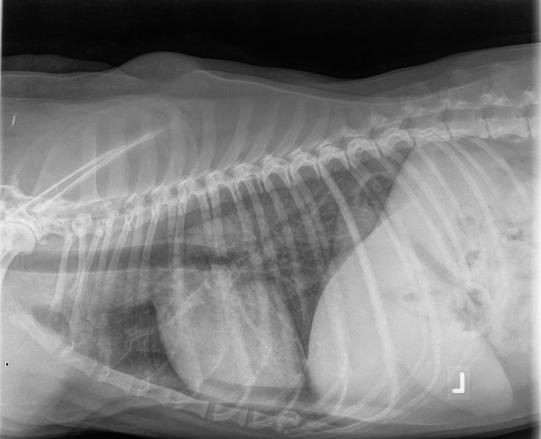

Der körperliche Untersuch ist weitgehend unauffällig, einzig die Leber fühlt sich vergrössert an. Auch eine Blutuntersuchung liefert keine schlüssigen Hinweise auf die Ursachen für die Symptome von Baghira, weshalb Röntgenaufnahmen des Brustkorbs angefertigt werden. Hier zeigt sich, dass die Lunge des Hundes diffus verdichtet erscheint. Für dieses Lungenbild könnten verschiedene Krankheiten verantwortlich sein, weshalb die Expertise eines Radiologen eingeholt wird. Neben einem Viralinfekt, Lungenblutungen oder einer sogenannten eosinophilen Pneumopathie erachtet der Röntgenspezialist insbesondere einen Befall mit Lymphkrebs als wahrscheinlich.